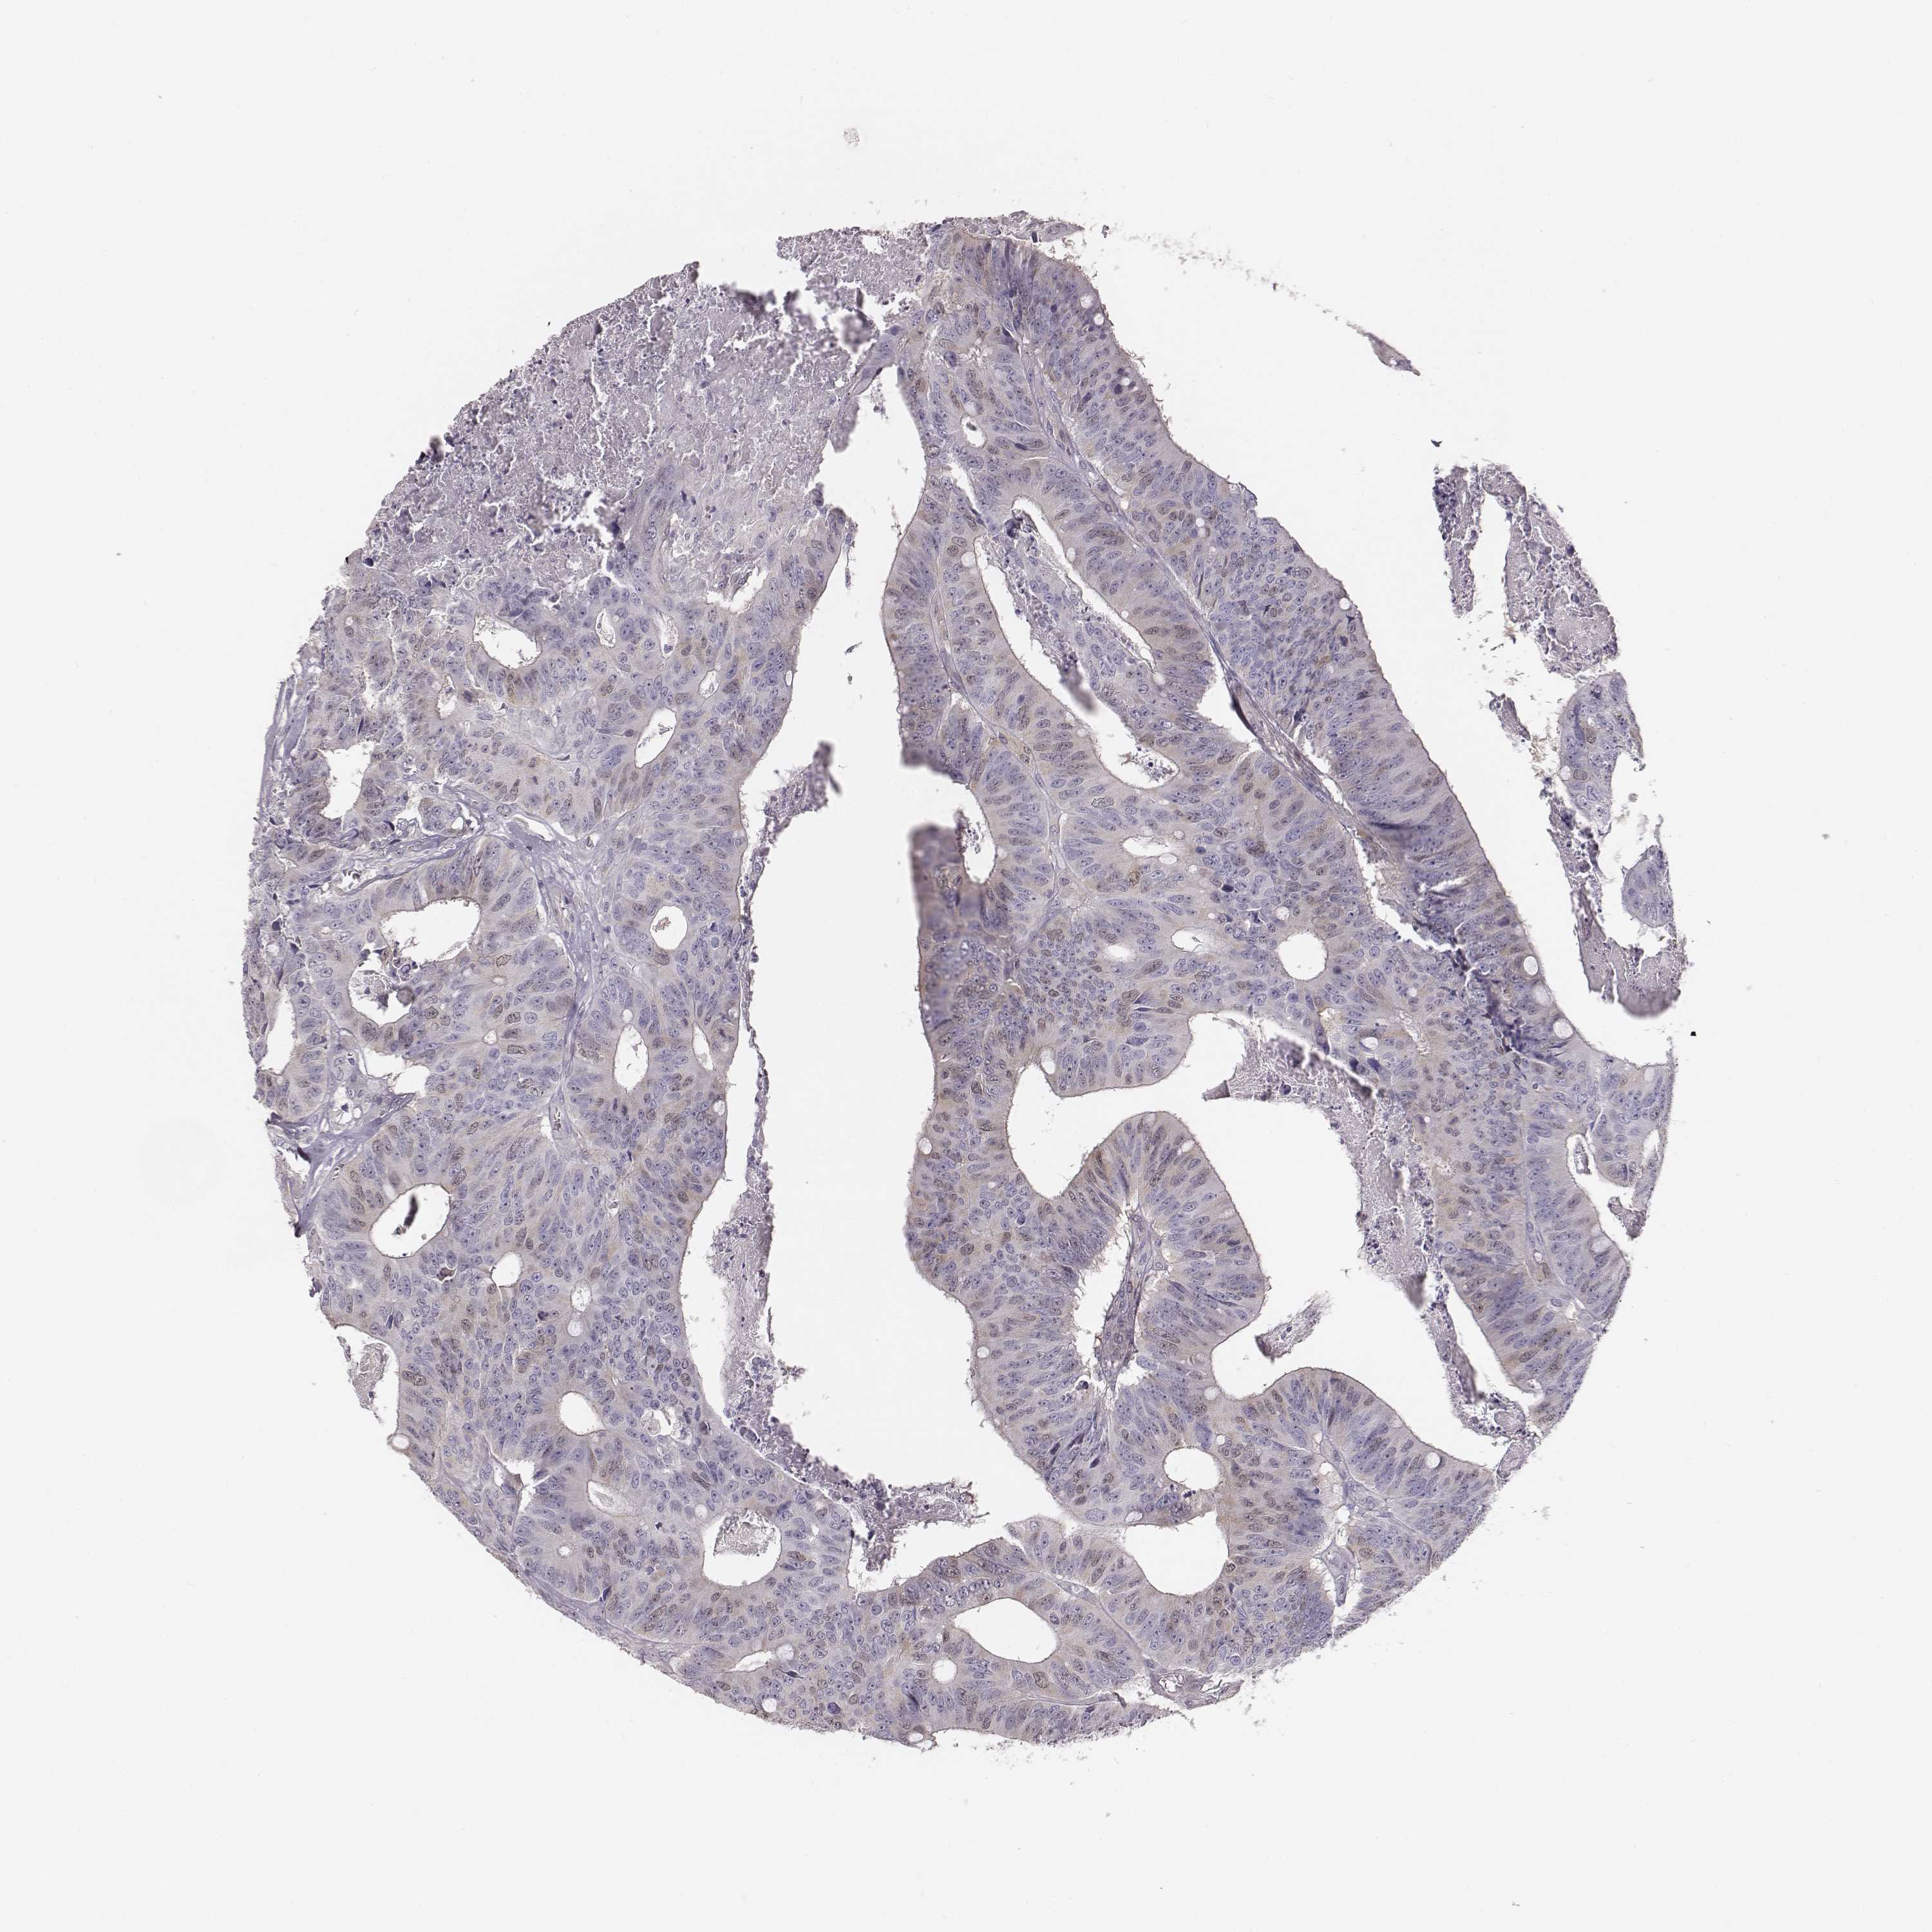

CANCER COLORECTAL CANCER Show tissue menu

Colorectal cancer

Human cancer

Colon adenocarcinoma